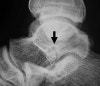

X-ray : 거골두 골절(Talus head fracture)